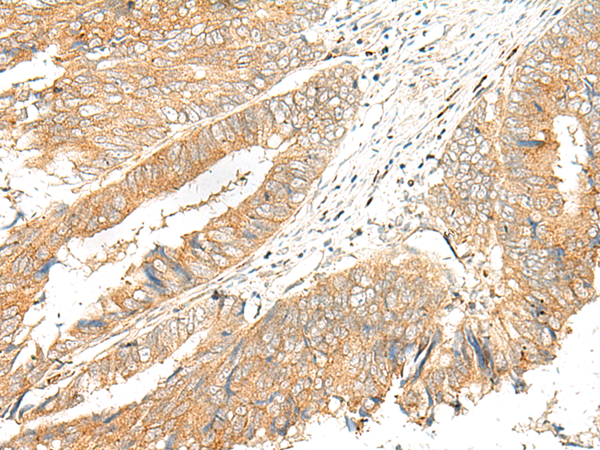

IHC positive control:

Human cervical cancer and Human colorectal cancer